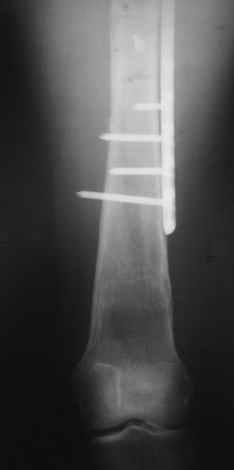

Уважаемые коллеги, приношу извенения за молчание. Готовили материал и боялись писать раньше времени. Все хотели убедиться в том, что после операции все будет спокойно. Спасибо за отклики и советы. К сожалению, гамма-гвоздя, штифтов с возможностью установки более 2-х блокирующих винтов у нас нет. Зато нашли достаточно длинную пластину с угловой стабильностью. После проведения предоперационной подготовки и планирования выполнили остеосинтез. В условиях рентгеноперационной, после репозиции дистрактором из одного разреза 5см в проксимальном отделе подкожно установили пластину. Пришлось выполнить дополнительный разрез до5см в проекции перелома диафиза в средней трети, из которого удалось репонировать перелом и выполнить фиксацию стягивающим винтом. Затем все завершилось наложением пластины с угловой стабильностью. Пластина оказалась достаточно длинной, что позволило перекрыть все переломы с фиксацией каждого отломка минимум 5-ю винтами. Синтез достаточно стабилен. Пациентка активизирована на 3-и сутки(снимки прилагаются). В настоящий момент пациентка выписана на амбулаторное лечение. Еще раз, огромное спасибо всем за помощь в выборе тактики и просто совете. С уважением Украинский Е.

Прошу прощения, со снимками глюк произошел. Высылаю. С уважением Евгений У.

Получилось очень симпатично, мои поздравления. А можно фото конечности без наклеек посмотреть?

И межфрагментарный винт на диафизе - так ли он нужен при выбранном варианте остеосинтеза с относительной стабильностью?